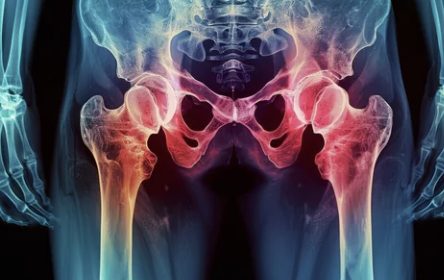

4️⃣ 고관절 수술 후 회복, 주의해야 할 점은 무엇일까요?

고관절 수술 후 빠른 회복을 위해서는 몇 가지 주의사항을 꼭 지켜야 합니다. 😊

- 수술 부위 관리: 상처 부위를 청결하게 유지하고, 감염 예방에 신경 써야 합니다.

- 낙상 예방: 낙상은 회복을 더디게 하고 합병증을 유발할 수 있으므로, 보조 기구를 사용하고 안전에 유의해야 합니다.

- 과도한 활동 자제: 수술 초기에는 무리한 활동을 피하고, 충분한 휴식을 취해야 합니다.

- 금연 및 금주: 흡연과 음주는 뼈와 연골의 회복을 방해하므로, 반드시 금해야 합니다.

- 정기적인 검진: 의사의 지시에 따라 정기적인 검진을 받아 회복 상태를 확인하고, 필요한 조치를 취해야 합니다.